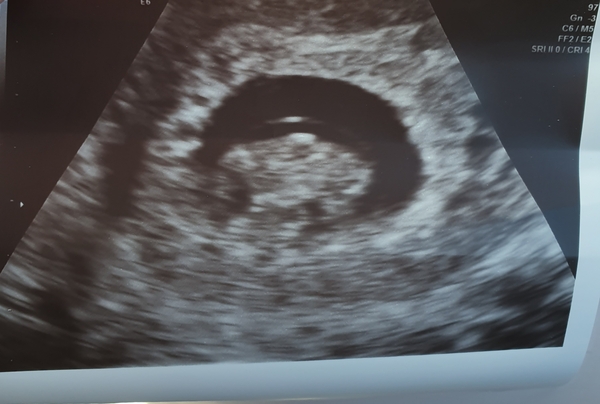

Also a loooooooonng 2 week wait i finally had my scan on Thursday and the little cookie has grown, continues to have a strong hb and is now officially 8 weeks.

What a lovely early scan picture too, and a massive relief that everything has grown 2 weeks later too!

Morning! Went for our scan yesterday, I was spot on with dates, 8+3 today! X

ah what a lovely scan pic!

couchroastpotato · 21/10/2019 12:24

Thanks @TwittleBee Grin my little kidney bean at the moment! Everything is perfect for this stage so I'm a bit more relaxed waiting for the 12 week scan now!! X